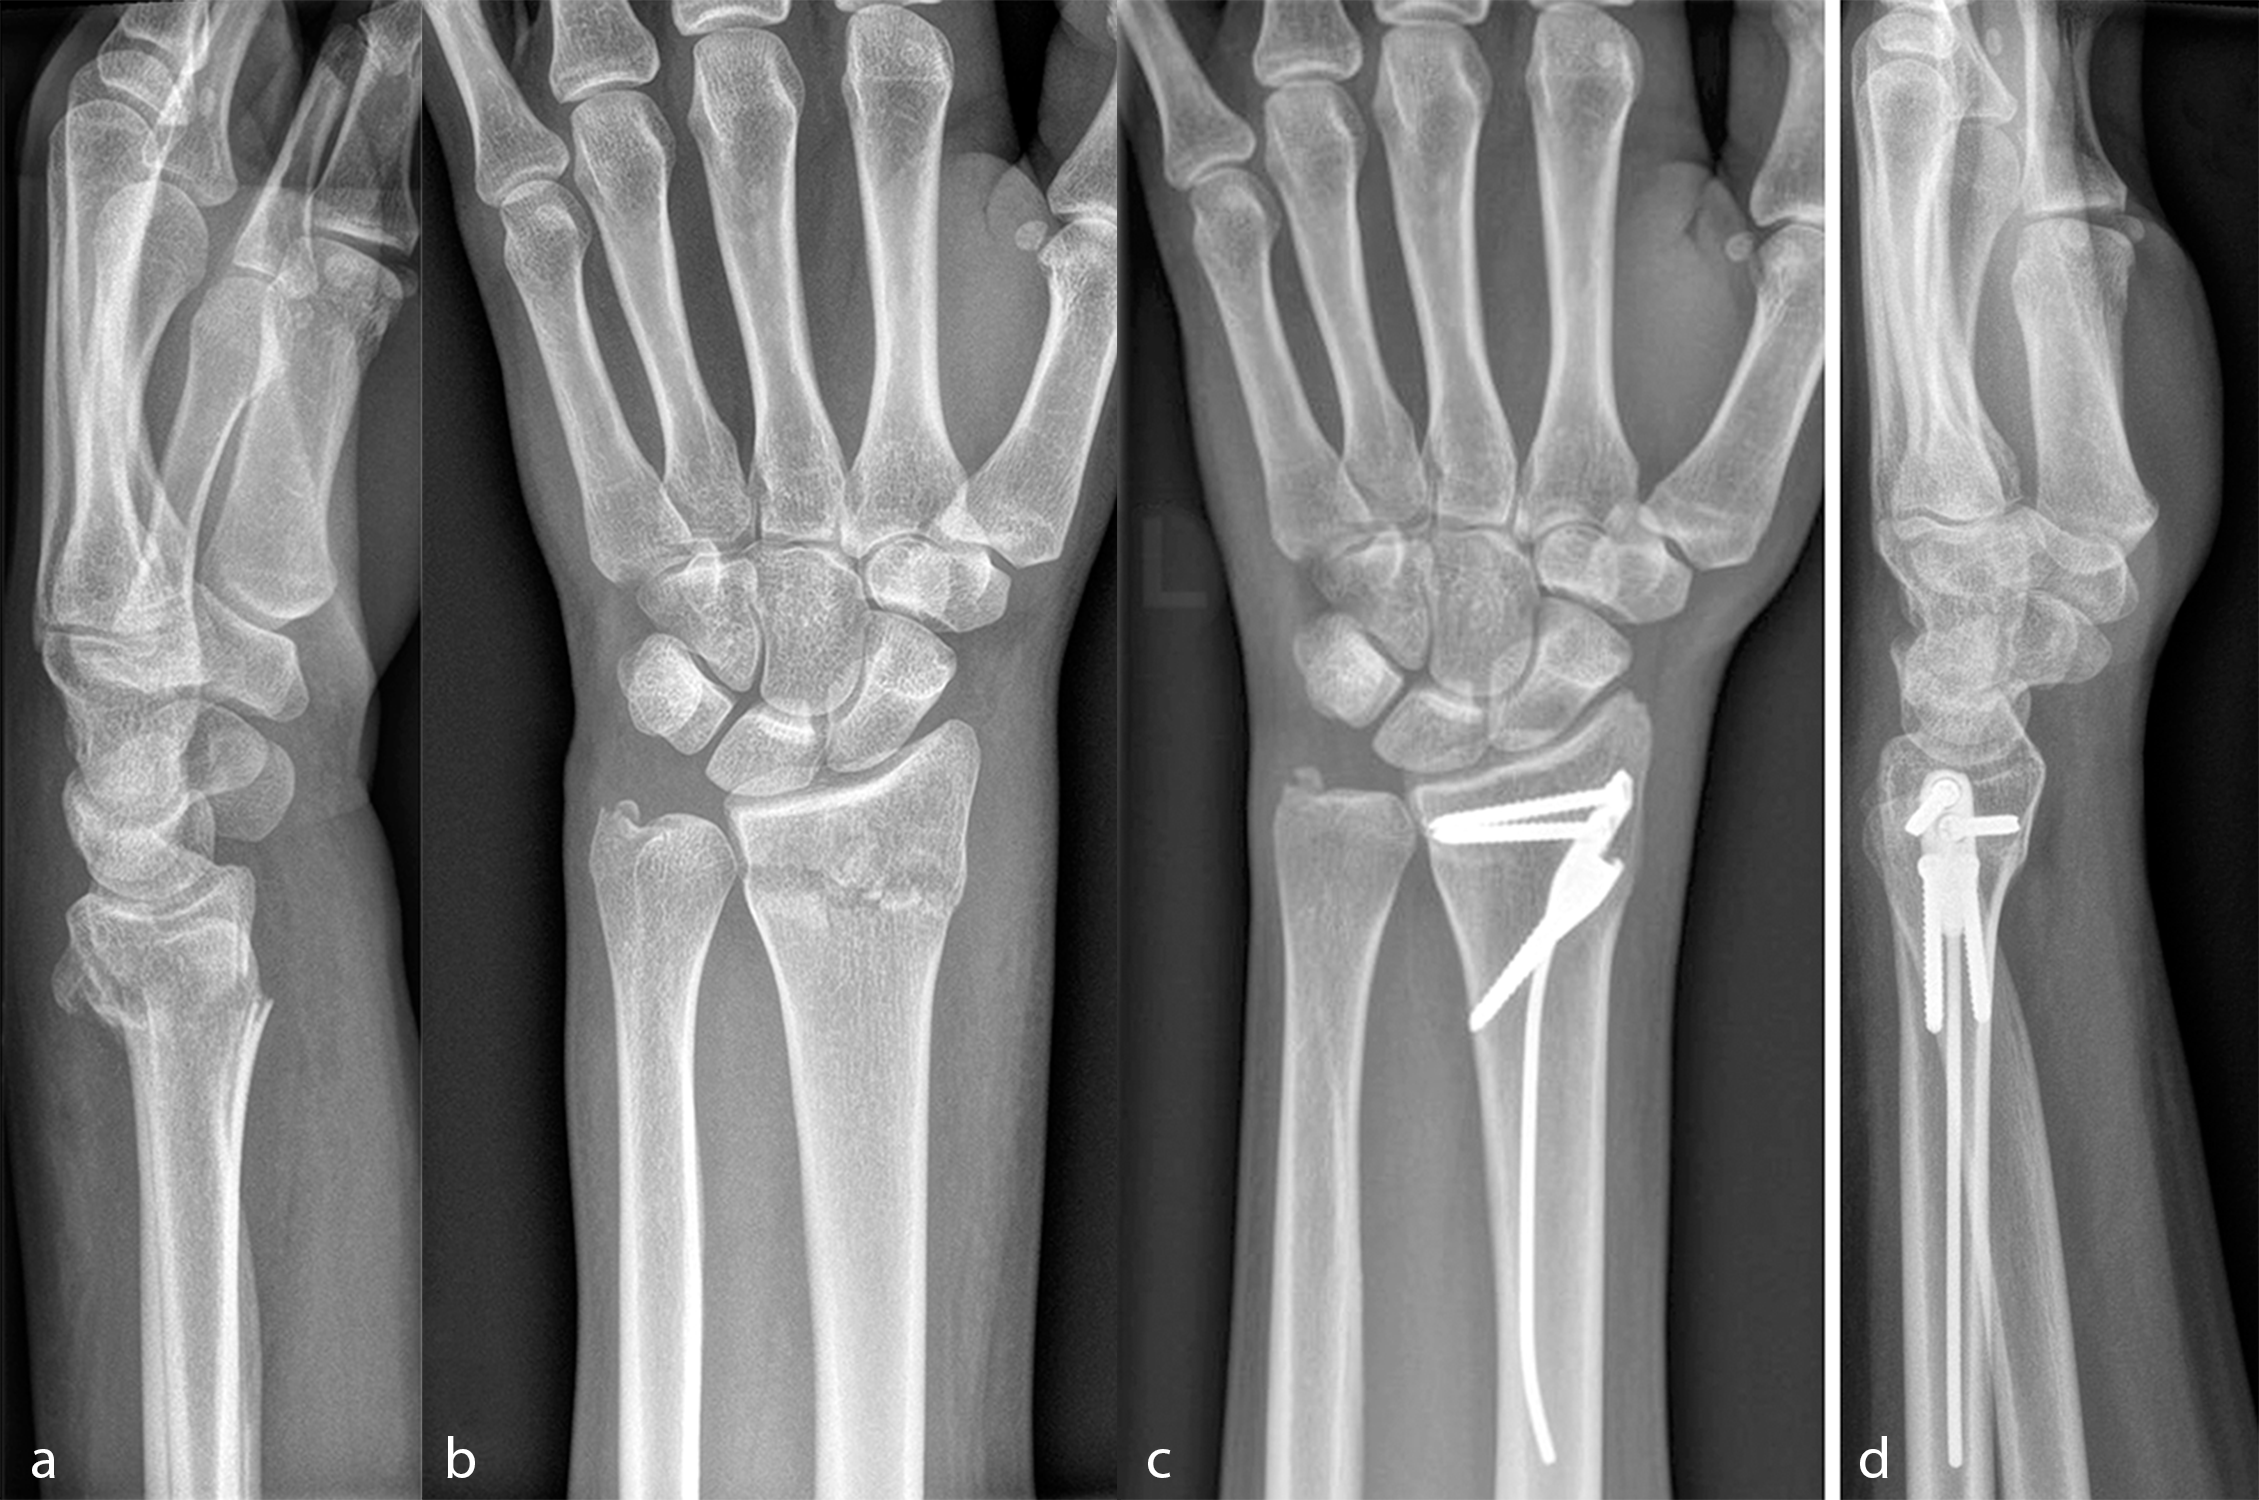

Approved by the AO in June 2022, the DRIM-Nail is an innovative treatment option for patients with extraarticular distal radius fractures. The design, development and certification of this new intramedullary nailing implant originally grew from a multi-partner collaboration between DISRAD AG, a start-up founded at Balgrist University Hospital by the Balgrist Beteiligungs AG, the University of Zürich, the AO Technical Commission's Hand Expert Group, the AO's Innovation Funding, and 41medical.

Consistent with the AO TC’s ethos of harnessing innovation to improve patient care and outcomes, the new DRIM-Nail provides all the benefits of minimally invasive intramedullary fracture stabilization, including minimal trauma to the bone fragments and the protection of the adjacent soft tissue. This aims to achieve faster recovery, better and faster functional and cosmetic outcomes, and a lower economic burden compared to current treatment options.